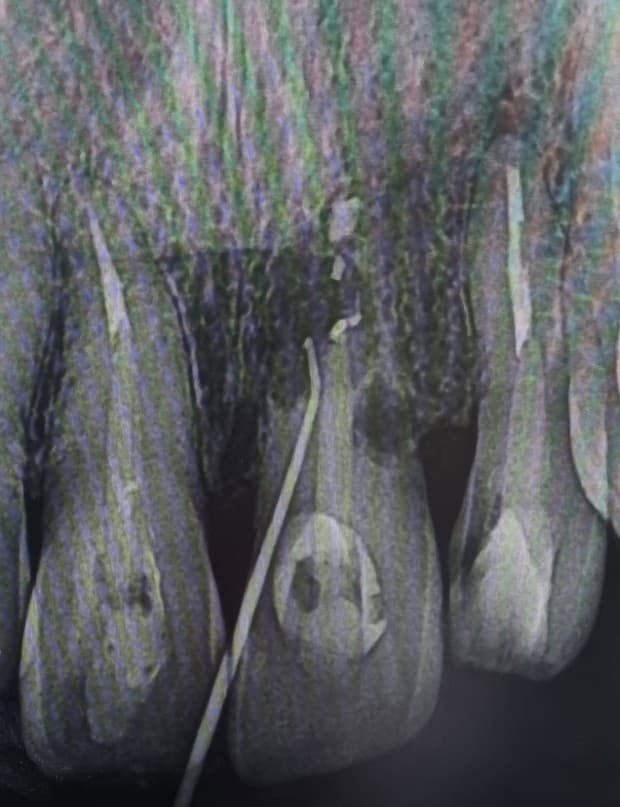

작년 11월 경 재식 치아 잇몸 위로 볼록한개 솟아 올랐는데 피곤해서 일시적으로 생긴 구내염인가 싶어 놔뒀는데 없어지지는 않고 빨갛던게 고름이 차더군요. 동네 치과 두 군데를 가니 대학병원이나 보존과 전문의가 있는 병원급 치과를 가서 치근단 절제술을 받아야 된다고 했습니다. 이미 신경 치료한 치아라서 재신경치료가 힘들다고 하면서요. 정보를 찾던 중 치근단은 임플란트 전 마지막으로 하는 조치라 집에서 조금 멀지만 재신경치료가 가능한 보존과 전문의를 찾아갔습니다. 방사선 사진을 찍고 확인 하면서 뿌리 손상 범위가 커 치근단을 하면 지탱하는 뿌리가 너무 부족하다, 그리고 뿌리 말고 잇몸 안쪽 중간 부분도 치아가 없어지고 있다, 재식치아에서 자주 그런 현상이 일어난다. 그래서 재신경치료를 할 수 있으나 별 의미가 없다는 진단이었습니다. 3개월에 한번 염증 관리나 하면서 쓰는데 까지 쓰다가 이상이 생기면 임플란트 하라는 답변이었습니다.

이 후 대학병원 보존과(전공의 진단)도 비슷한 답변이었고, 병원급 치과 보존과 선생님은 잇몸 열어서 병변 제거 후 MTA충전해서 3년 정도 더 사용해보자 하셨는데 CT 결과를 보시더니 안하는게 나을 것 같다 하시며 빠른 시일내에 임플란트를 하라고 하더군요.

방사선 사진을 보면 치아 뿌리와 옆 부분이 많이 상실되어서 어딜 가나 비슷한 답변을 받겠다 싶어 방금 언급된 병원급 치과 임플란트 상담을 하였습니다. 뼈가 두꺼워서 식립은 가능하고 그래도 뼈 이식은 해야 되며, 현재 올라간 잇몸보다 임플란트를 하면 잇몸이 더 올라가니 잇몸이식으로 옆 치아와 라인을 맞춰주겠다 그리고 아랫니가 조금 튀어나와있으니 임플란트를 하면서 약간 삭제가 들어가야 되겠다였습니다.